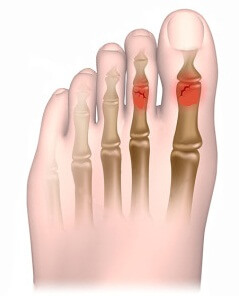

Признаки перелома пальца на ноге делят на достоверные и вероятные.

К последним относится:

• Наличие боли в пальце.

• Отечность и гиперемия, сопровождаемые повышением температуры в области повреждения.

• Неестественное положение пальца.

Достоверные симптомы перелома пальца ноги:

• При ощупывании выявляется дефект фаланги.

• Поврежденный палец выглядит короче.

• Невооруженным глазом видна деформация фаланги.

• Крепитация костных отломков.

• Патологическая подвижность кости.